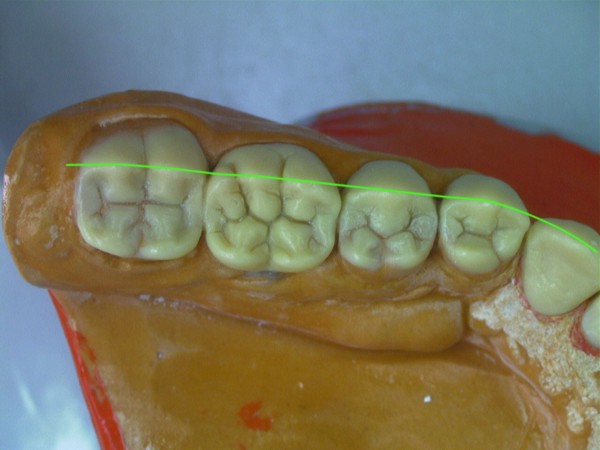

RESUMEN Es un desafío complejo conseguir una secuencia lógica de trabajo en la reconstrucción para una rehabilitación. SUMARY: Trying to acquire a logic working sequence in oral rehabilitation always becomes a defying challenge. The order of the different elements that deal with the whole dental system, as well as its positioning in each one of its planes, turn out into a series of rather difficult details that must be taken into consideration if we really aim towards satisfying results. Alineación Tridimensional- Macrotrípode de la Oclusión- Guía anterior- Microplanos. KEY WORDS: DESARROLLO: Las bases de todo el proceso tienen sus orígenes en una fuente de información tan fidedigna como es el concepto de la ALINEACIÓN TRIDIMENSIONAL La alineación dentaria en relación a unos parámetros regidos por la ATM y la guía anterior constituyen el MACRO TRÍPODE DE LA OCLUSIÓN creando una permanente dependencia de todo el sistema dentario con este; durante el cierre mandibular (la centricidad dentaria) así como durante los movimientos excéntricos (lateralidades y todas sus variantes intermedias). Dependencia que se vera incluso reflejada en detalles tan poco vistosos como son algunos factores elementales de la oclusión: la dirección de surcos. Así pues para sintetizar la totalidad del proceso de una forma breve pero clara destacaremos a continuación los conceptos fundamentales que se tuvieron en cuenta a lo largo de este trabajo. Dado lo extenso del tema nos centraremos fundamentalmente en: A- El desarrollo de La GUIA ANTERIOR, ya que consideramos que da origen al resto del proceso, B- Los VÍNCULOS DIRECTOS entre esta y los sectores posteriores. De la misma manera se muestran casos de estudio de pacientes semejantes al tratado, en que por cuestiones docentes se ha recurrido al encerado de estudio progresivo con ceras de diferente color a fin destacar donde empieza el desarrollo de cúspides, el origen de las crestas internas, así como los rebordes y el alineamiento a que están sujetos cada uno de estos elementos dentro de la individualidad cada pieza. A-GUIA ANTERIOR: Arco Esqueletal, Formas de Empotramiento, Alineamiento. Aunque en ocasiones pueda parecer que se forman situaciones por generación espontánea dada la escasez de información, siempre existen pequeños datos que nos proporcionan claves de referencia para empezar una reconstrucción. La que nos ayuda de una forma destacada y que no necesita de un vínculo directo con los dientes adyacentes, es la relación que se establece entre las piezas 31 y 41 y el movimiento de rotación del conjunto mandibular durante el cierre. Visto desde Sagital, si trazamos una línea entre la base de la emergencia de los centrales y la cabeza de cóndilo del articulador y a continuación proyectamos a 90º una segunda línea, hallamos la equivalencia al eje axial de la pieza (no así la altura). Este detalle nos puede suponer una gran diferencia en casos en los que el capital oclusal esta severamente dañado, allá donde no tenemos referencias anatómicas contiguas a la pieza que reconstruimos( fig 1). A partir de ello podemos empezar a considerar las proporciones en el eje vertical de la pieza ya bien sea a través de información remanente de los cíngulos linguales y de su tamaño en relación al resto del diente, o en ausencia total del capital oclusal (como es el presente caso) en base a las proporciones vestíbulo-linguales proyectadas a lo largo del eje vertical de la pieza. Las proporciones de centrales y caninos inferiores desde un plano horizontal reparten cada una de las caras libres en igual medida desde su borde incisal (50% Vestibular-50% Lingual), de manera que si proyectamos el borde de la primera pieza que hemos construido a partir del arco esqueletal , hacia la superficie que el lateral y canino ocupan en su emergencia (o siguiendo los rebordes/ alveolo en su defecto) podremos situar de una forma precisa el ecuador máximo de cada diente en sus caras libres, alineando así su conjunto (fig. 2). De la misma manera disponemos de unas proporciones entre el ancho V-L de la terminación amelo dentinaria de la pieza y el largo coronario (ej. El largo del canino inferior es aproximadamente eldiámetro V-L + un 30%). Dicha medida la prolongamos por el eje axial de la pieza para obte A partir de éste punto empezamos a pensar en la situación de las piezas superiores. La Dimensión Vertical, Centralizará la Mandíbula y nos aportará la El propio acoplamiento de los caninos de por sí implican una cantidad de desoclusión de las piezas (componente vertical), así como una calidad de desoclusión (componente horizontal del desplazamiento mandibular). Cabe destacar que para asegurar el buen funcionamiento de una guía anterior siempre es más favorable un punto de acoplamiento alto (desde un plano sagital seria una inserción notable del borde incisal inferior contra la vertiente palatina del superior, permitiendo así un importante recorrido en la desoclusión), así como una componente del canino superior muy verticalizada, lo cual impide que el maxilar inferior padezca un movimiento excentrico muy pronunciado, otorgando un patrón de movimientos mucho más verticales con menor distancia recorrida hasta el borde a borde entre caninos (evitaremos caer, eso si, en unos ejes de piezas convergentes -Clases 2/II-, situaciones con un alto grado de contención.) Asi pues prolongamos el eje del canino a partir de su perfil de emergencia. Respetamos las proporciones vestíbulo-linguales en 1/3 a 2/3 (fig. 3-4-5) y lo modelamos en vertical hasta una altura un 25 % mayor que su diámetro V-L a nivel cervical. Ello nos definirá un acople que una vez realizado en ambos caninos tendrá cuantificados unos valores de suma importancia que arrastrarán consigo todo el peso de la centricidad mandibular durante el cierre, así como la dimensión vertical o las propiedades desoclusivas, pues podremos observar como al realizar la lateralidad ya obtenemos espacios de separación uniforme en los cuadrantes posteriores allá donde todavía no hay piezas. Lo mismo hacemos con los centrales: proyectar canal radicular (en el encerado) si lo hay, respetar el ancho de cada una de las caras libres visto siempre desde un plano horizontal a la pieza, y proyectamos en vertical el diámetro cervical + 40-45% para terminar el largo de la pieza. Es importante no confundir la exposición de las caras vestibular y lingual de los dientes observándolos desde un plano horizontal como pieza individual, frente al mismo hecho visto desde su posicionamiento en el modelo, donde las piezas anteriores no se encuentran perpendiculares, sino ligeramente inclinadas hacia vestibular en su borde incisal, con lo cual sus vertientes palatinas se ven más expuestas. En esta fase ya tendremos un acoplamiento a partir del cual visualizar la Protrusiva y los movimientos intermedios compartidos con los caninos durante la función compartida de la guía anterior (fig. 6). Es lógico pensar que cualquier individuo que ha pasado por un proceso tan destructivo como este habrá sufrido movilizaciones a lo largo del tiempo y por lo tanto todas estas aportaciones teóricas son aplicables en la medida en que estemos dispuestos a hacer pequeñas variaciones tan solo milimétricas durante este proceso de alineado. En general cabe hacerse a la idea de que si bien los valores anatómicos / proporciones son prácticamente absolutos, no son igualmente cuantificables los movimientos o alteraciones a que ha sido sujeto un individuo que llega a este nivel de tratamiento (incluidos variaciones en exposición de reborde/alveolo por reabsorción), si bién es cierto que las leyes de proporciones dentarias y alineamiento conjuntamente tratadas pueden llevarnos a recuperar un orden desaparecido en una boca enferma. B-Elementos Intermedios: Escalones Negativos, Áreas de Transición y Microplanos. es mejor alinear el inferior y con ello se podrá acoplar todo el superior sobre él (resulta un tanto más complicado alinear bases de crestas triangulares y rebordes superiores antes que puntas de cúspide inferiores) (fig 7). Esta vendría a ser una referencia inmediata, pero hay que considerar otras. Entre ellas resaltar que según los biotípos se encuentran escalones o saltos negativos en el punto de transición entre anteriores y posteriores. Estos cambios de nivel van directamente asociados al potencial desoclusivo que genera la guía anterior frente al resto de piezas y son elementos funcionales que deben respetarse si se desea preservar la absoluta funcionalidad del conjunto. Este exceso anatómico marca una importante diferencia ya que su inserción en la cara antagónica de los caninos superiores es lo que proporciona la condición a la oclusión de mutuamente protegida. Dependiendo de los biotipos estos escalones pueden ser mayores o menores (fig 8). Al igual que los escalones, van apareciendo según avanzamos hacia los cuadrantes posteriores áreas de transición que suponen una proyección del desarrollo de los cíngulos, con el consecuente aumento del área cortical de las piezas, hasta el desarrollo de cúspides. Detrás de ello encontramos todo un compendio de proporciones que se respetan por igual en todas las denticiones que estudiamos, tanto en lo que respecta al ancho oclusal de cada elemento con las proporciones desde cada una de las caras libres (60% cusp de trabajo-40% cusp de corte) hasta las proporciones de la cara interna o el propio alineamiento de las bases de las crestas internas de las cúspides (fig 9). Normas que como se puede apreciar se han considerado incluso para prever las formas de piezas tan elementales como son las espigas y pernos asi como de la estructura de metal empleados en este caso gracias al encerado La información que aportamos en las fases iniciales siempre se puede alterar y modificar en este proceso de búsqueda de datos. Un proceso en el que sin duda el conocimiento anatómico, los biotipos y sus relaciones entre ejes, así como las relaciones craneométricas que desembocarán en el alineamiento de curvas, nos va a llevar a recopilar infinidad de datos vinculados entre si que permitan de una forma segura, enfocar con precisión un trabajo de estas características. «Tal como se aclara en la segunda entrega, la simbiosis entre clínico y técnico es prioritaria para obtener los logros fundamentales de una OCLUSIÓN ORGÁNICA. Si cuatro son las manos ejecutoras de una rehabilitación como la presentada,debo hacer hincapié en la excelencia de la labor clínica ejecutada por el Dr.Carlos A. Acuña Priano, en la preparación de muñones con alta precisión donde la lectura de los límites fué más que objetiva, como asi la concepción toda de un caso de alta complejidad no solo en el aspecto estructural y médico, sino también en el manejo de una personalidad dificil y controvertida de un paciente extremadamente destruido. El Dr.Carlos A.Acuña Priano,Odontólogo,Master en Implantología y Rehabilitación Oral,de amplia formación en temas de Oclusión, ha enriquecido mi labor de laboratorio como ya lo hiciera nuestro común maestro, el Profesor Anibal Alonso. A ambos, muchas gracias. Pedro Colomina Cursante de estudios de prótesis dental en la escuela Ramon y Cajal de Barcelona (1988)

De la misma forma que en lo expuesto hasta ahora, en los elementos intermedios de la oclusión (cuadrantes posteriores) prevalece el alineamiento por encima de todo. Un alineamiento que se aplica tanto a la morfología individual así como a la disposición de las piezas entre sí (alineación de conjunto).

Todo ello no viene a ser mas que un grupo de normas en la disposición individual de las piezas para dar un alineamiento de conjunto a todo el sistema, y de esta manera conseguir realizar la suma de Microplanos que creados por la cara oclusal de cada pieza conforman las ya conocidas curvas funcionales de Spee y de Wilson, todas ellas encaradas de tal manera que crecen y se desarrollan desde la guía anterior hasta llegar a ser proyectadas a la cabeza de condilo, tanto en el plano frontal, como sagital (fig 13-14-15).